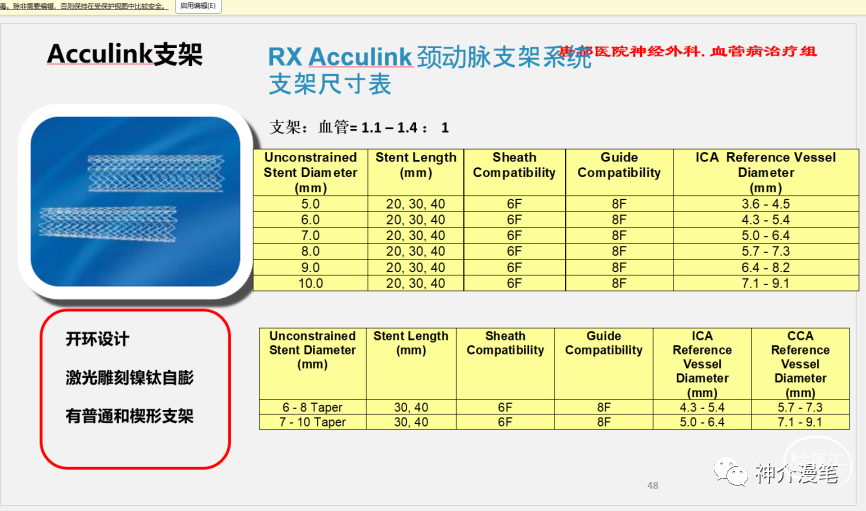

雅培系列支架

雅培上面两款支架一个开环,一个闭环,应用的场景,使用原则和上诉所说的支架大体差不多,大家可以再看一下他们的具体型号和尺寸。酌情使用,比较有意思的是这两款支架的释放都是“半自动化的”,支架到位后通过旋转释放手柄或回拉把手即可完成。不需要前面几款支架的推扒技术,所以一旦支架到位良好,释放极度简单,几乎就是傻瓜式释放,特别适合新手小白使用。